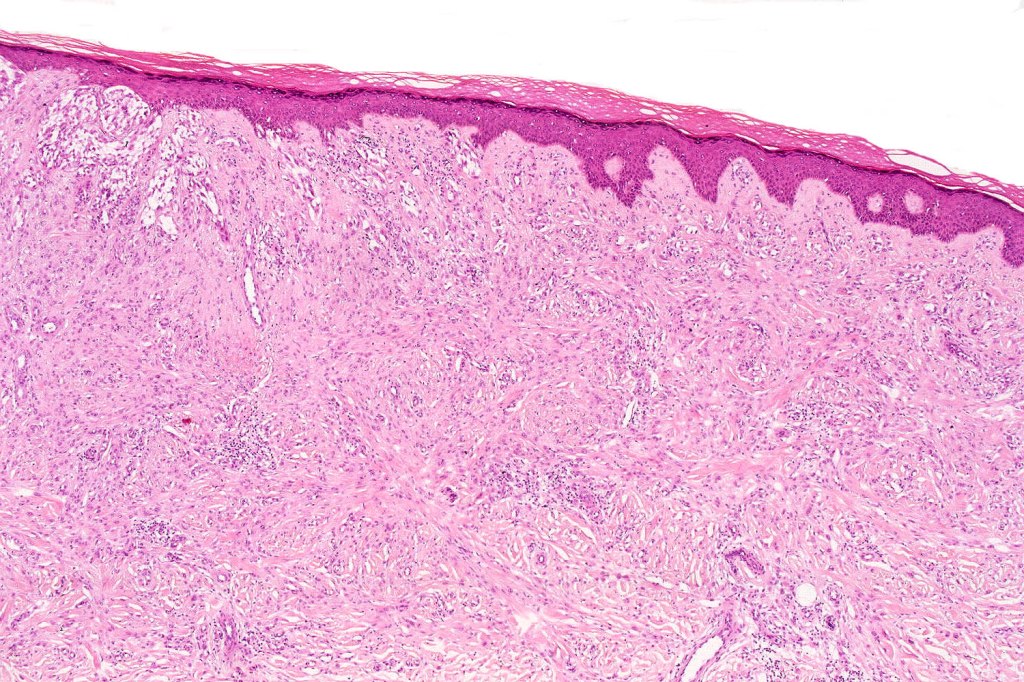

•Hyperkeratosis

•The epidermis is generally normal although sometimes acanthosis is evident

•Silhouette is either wedge-shaped or plaque-like

•Residual Spitzoid junctional nests sometimes evident